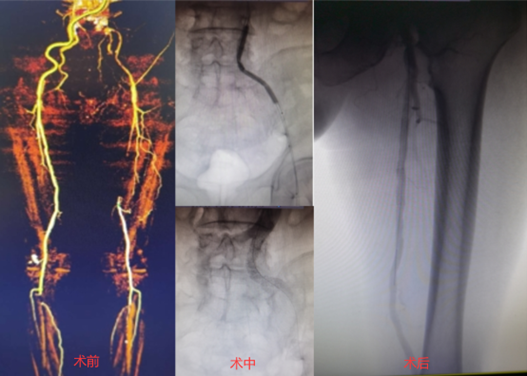

病例分享

病例1:為股淺長段閉塞病變,術(shù)者采用了knuckle技術(shù),選擇Command 18導(dǎo)絲順利通過病變。

病例2:為股淺長段CTO病變,術(shù)中多次嘗試,開通極其困難,使用Connect Flex導(dǎo)絲后順利通過閉塞段。

病例3:為Command 18聯(lián)合Connect flex導(dǎo)絲順利治療的髂開口閉塞合并股淺長段CTO病變;術(shù)中首先采用逆向技術(shù),穿刺股總動脈,開通髂動脈;隨后使用Connect flex導(dǎo)絲順利開通股淺遠(yuǎn)端長段CTO病變。